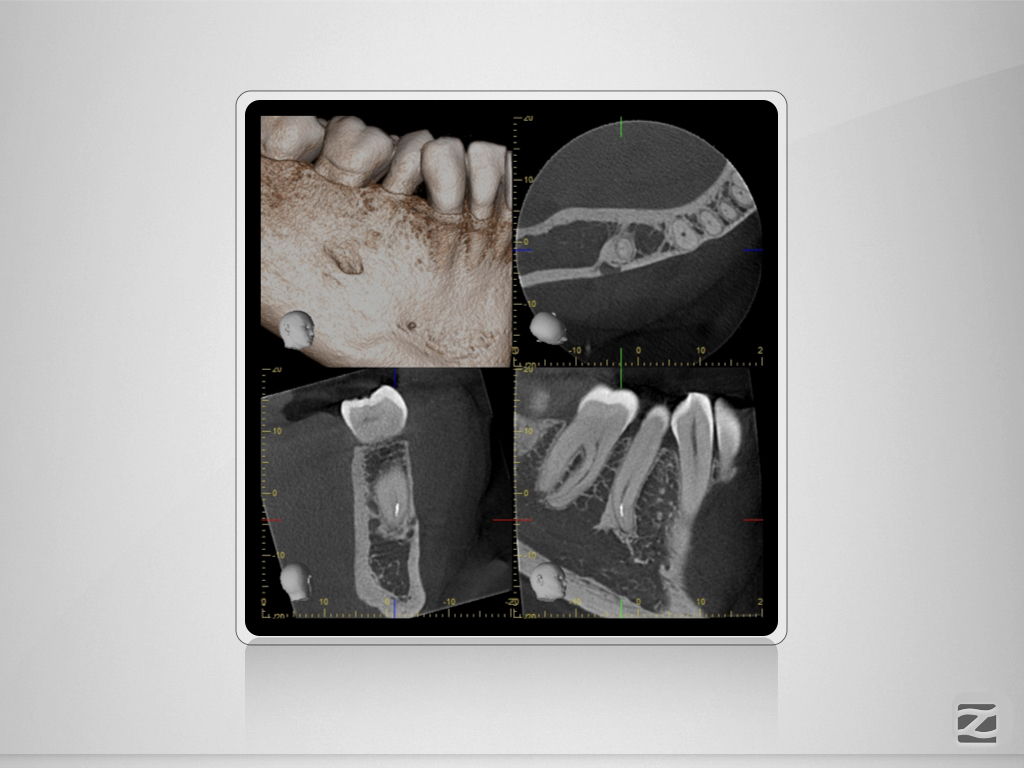

44D.006

Prämolaren sind (nicht) einfach!